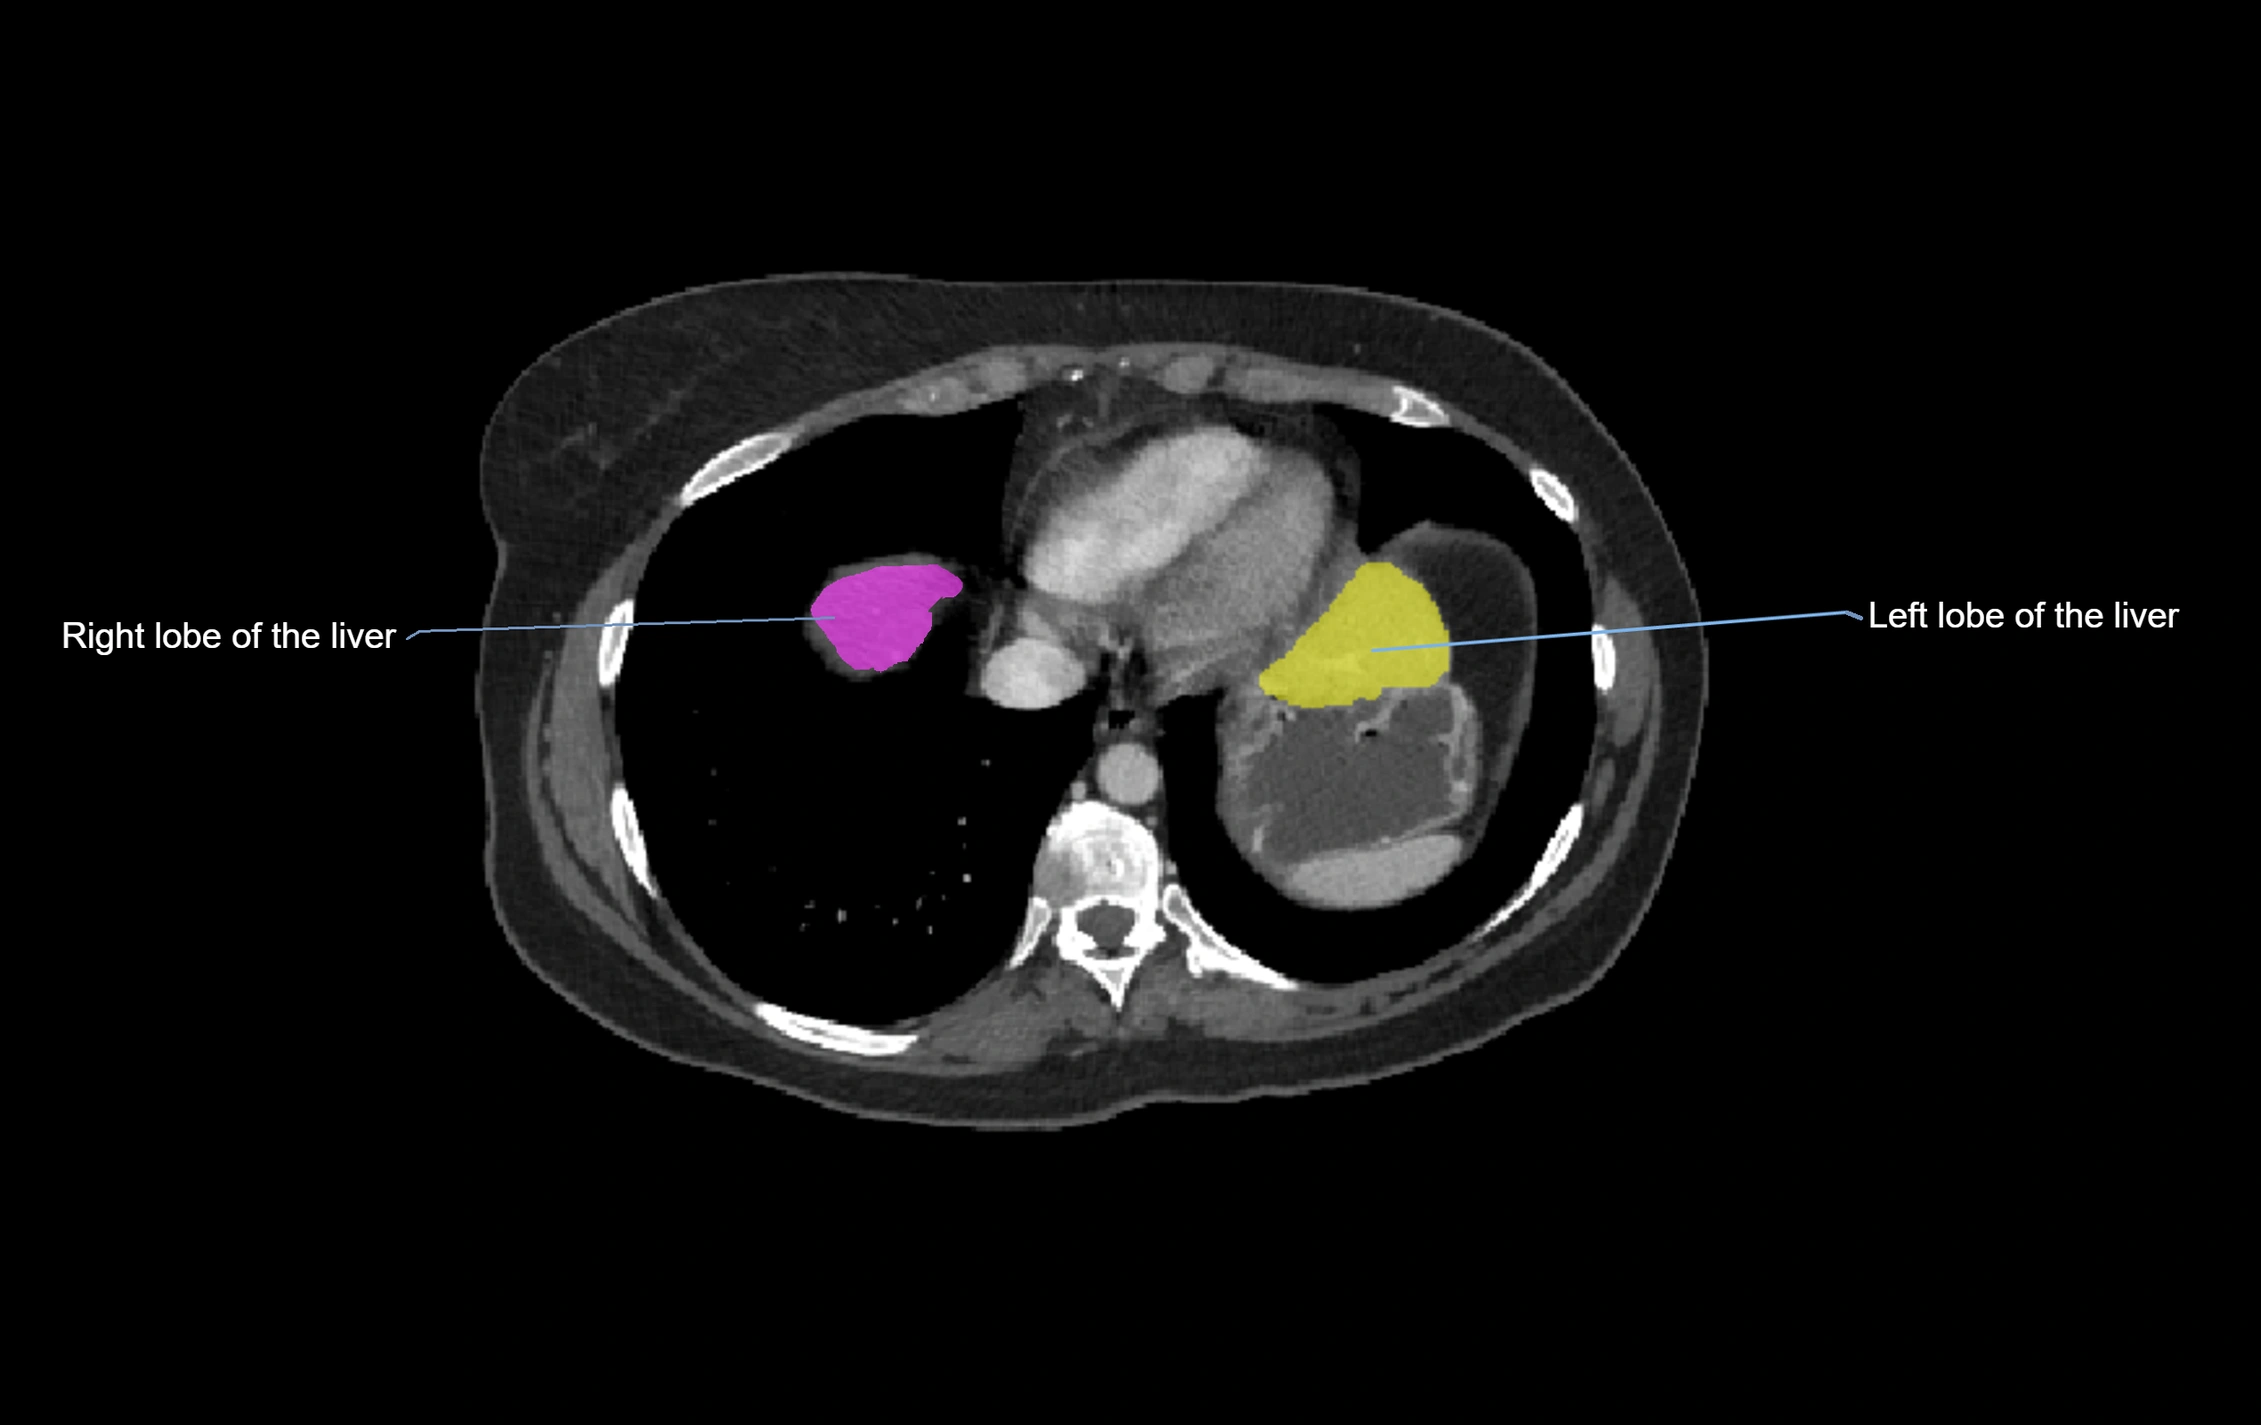

The caudate lobe of the liver is a distinct anatomical subdivision of the liver, designated as segment I in Couinaud’s classification. It lies on the posterior surface of the liver, between the fissure for the ligamentum venosum (left boundary) and the groove for the inferior vena cava (IVC) (right boundary). Superiorly, it is related to the posterior liver surface, and inferiorly it is separated from the left lobe by the porta hepatis.

The caudate lobe is unique because it receives dual portal venous and arterial inflow from both the right and left portal veins and hepatic arteries. It also has independent venous drainage directly into the IVC via multiple small hepatic veins, unlike other lobes that drain through the three main hepatic veins.

This anatomical autonomy makes the caudate lobe especially significant in liver surgery, transplantation, and hepatic venous outflow obstruction syndromes (e.g., Budd–Chiari syndrome). Enlargement of the caudate lobe is a characteristic imaging feature in chronic liver disease and cirrhosis.